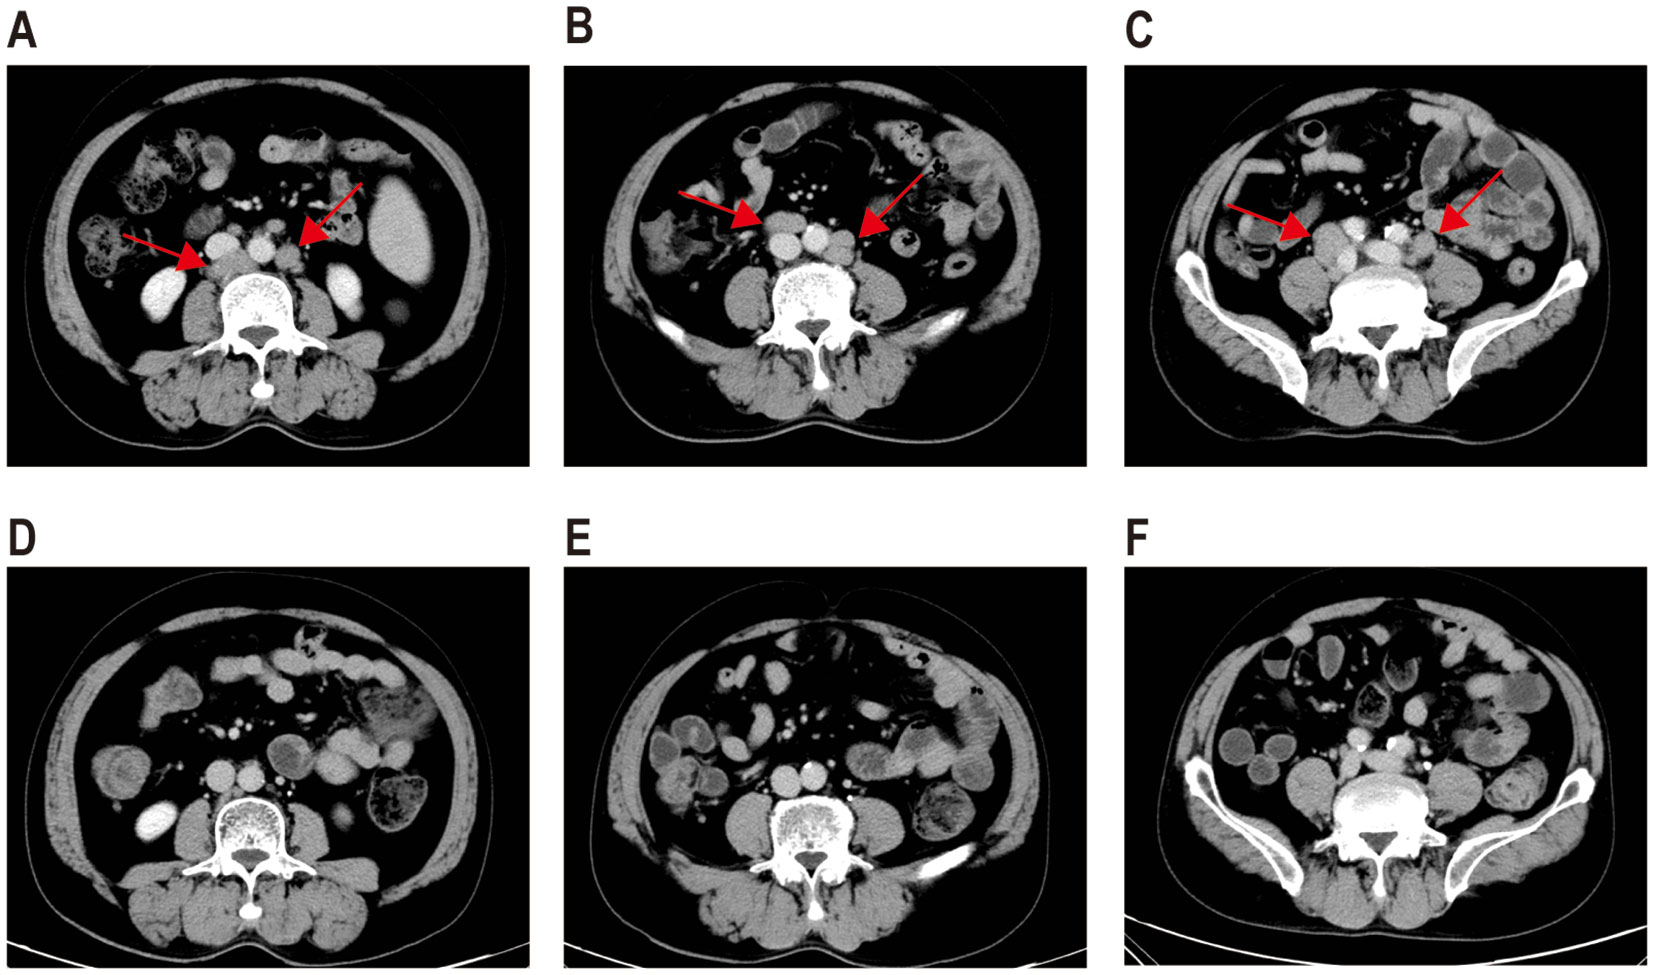

A 56-year-old male presented to a local hospital with a two-month history of right neck lymph node enlargement. He underwent a biopsy of the left paracervical lymph node. Biopsy results led to a diagnosis of DLBCL by local pathologists. Flow cytometry analysis of bone marrow puncture revealed monoclonal B lymphocytes expressing CD19, CD20, CD11c, and Ki-67 and lacking CD5, CD10, CD25, CD38, CD103, and CD123 expression. The patient was admitted to our hospital for treatment. Pathologists in our hospital reviewed the pathological section and made a diagnosis of PBL. Immunohistochemistry showed positive CD38, CD138, CD19, CD22, CD79a, Mum1, and kappa chain; negative CD3, CD5, CD10, CD20, PAX-5, BCL2, BCL6, C-myc, CD56, cyclin D1, ALKp80, CK, EBER, EMA, and lambda chain; 10% CD30 positivity; FDC network-positive staining for CD21; and a Ki-67 positivity rate of 60%. PET/CT examination showed increased radiation uptake in the nasopharyngeal region, tonsils, and many lymph nodes above and below the diaphragm, with a maximum standardized uptake value of 15.5 (Figure 1A).

Figure 1. PET-CT images and biopsy of lymph node of a patient with plasmablastic lymphoma. Pre-treatment PET-CT (A), PET-CT after four cycles of first-line therapy (B), and PET-CT three months after CD19 and CD22 CAR-T treatment (C). A biopsy of the right pelvic mass was conducted prior to CAR-T therapy. Wright–Giemsa staining revealed abnormal cells characterized by diffuse proliferation and infiltration, large size, abundant cytoplasm, round or slightly irregular nuclei, prominent central nucleoli, and frequent mitotic figures (D). Immunohistochemical analysis demonstrated that tumor cells were positive for CD38 (E), CD138 (F), CD19 (G), and CD22 (H) and negative for CD20 (I).

The patient was diagnosed with stage IV PBL and was treated with a regimen consisting of bortezomib in combination with etoposide, dexamethasone, cyclophosphamide, and doxorubicin (EDCH) (bortezomib 2.6 mg d1, 4; etoposide 0.1 g d1–4; dexamethasone 20 mg d1, 2, 4, 5; cyclophosphamide 750 mg/m2 d1; doxorubicin liposome 60 mg d1, q3w). The patient achieved CR after four cycles of first-line treatment. The Deauville Score by PET-CT was three (Figure 1B). Consolidation with autologous stem cell transplantation was suggested but declined by the patient because of financial constraints. He received bortezomib in combination with the EDCH regimen for two more cycles. At one month after the completion of six cycles of EDCH chemotherapy and bortezomib, CT scan indicated disease progression. Multiple enlarged lymph nodes were observed in several areas above and below the diaphragm. The largest lymph node, measuring approximately 2.9 cm × 1.6 cm, was in the left neck. The spleen was larger than previous scans, indicating possible involvement.

The patient received second-line treatment: daratumumab combined with GemOx for two cycles (daretuzumab 800 mg qw; gemcitabine 1 g/m2 d1, oxaliplatin 100 mg/m2 d1, q2w). CT scans revealed disease progression after two cycles of second-line treatment (Figures 2A–C). The largest lymph nodes were in the pelvic cavity, with a cross-section of 4.8 cm × 2.4 cm. A biopsy of the right pelvic mass was performed. The pathological results indicated the presence of PBL. Tumor cells were positive for CD38, CD138, CD22, CD79a, MUM1, CD45, and kappa; partial positive for CD19 and EBER; negative for CD2, CD3, CD5, CD10, CD20, CD56, cyclin D1, ALKp80, HHV-8, MPO, lambda and IgG; and 5% positive for CD30; the Ki-67 positivity rate was 70% (Figures 1D–I). Immunostaining revealed CD19 expression in 15% of tumor cells and CD22 expression in nearly all cells (95%). As CD19 and CD22 are targets of CAR-T cell therapy, CAR-T therapy was considered as third-line treatment.

Peripheral blood was collected for the generation of two distinct CAR-T cell products targeting CD19 and CD22, respectively. The CD19-directed CAR-T cells feature an anti-CD19 single-chain variable fragment (scFv), fused to a CD8α hinge and transmembrane domain, a 4-1BB (CD137) costimulatory domain, and a CD3ζ intracellular signaling domain. The CD22-specific CAR-T construct followed a similar design, with the anti-CD19 scFv substituted by an anti-CD22 scFv. The patient received cyclophosphamide and fludarabine for lymphodepletion. CD19 CAR-T cells (2.9 × 106/kg) followed by CD22 CAR-T cells (3.7 × 106/kg) were transfused sequentially to the patient with an interval of six days. White blood cells and neutrophilic granulocytes decreased after chemotherapy, but without neutropenia (Figure 3A). The patient showed no cytokine release syndrome response after CAR-T therapy. Ferritin slightly increased on day 4 following CD19 CAR-T transfusion (Figure 3A). CAR-T cells increased following transfusion and were detectable three months after transfusion (Figure 3B). One month after CAR-T transfusion, CT scan showed no enlarged lymph nodes (Figures 2D–F). Three months later, PET-CT showed a complete metabolic response (Figure 1C). Since the CAR-T transfusion, the duration of complete remission was more than 12 months until this submission.